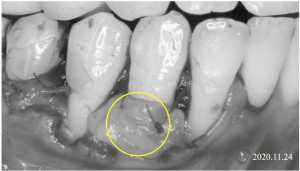

※リグロスを口蓋から採取した結合組織に塗布している様子

※結合組織移植術

歯ぐきの移植(結合組織移植)について

歯ぐきを歯の方向へ移動できるようにフラップ(歯ぐきの組織)を形成したあと、歯ぐきが薄い部分に対して結合組織移植を行いました。

上の写真では、黄色の丸で囲っている部分が、移植した結合組織の位置になります。

このように歯ぐきの厚みを補うことで、

-

歯ぐきの安定性を高める

根面被覆の結果をより安定させる

ことが期待できる場合があります。